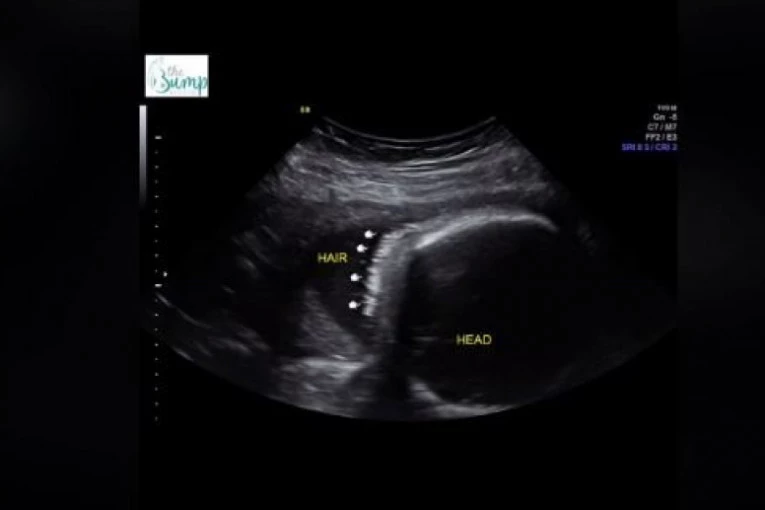

Jedan od tih pregleda bio je zakazan za 26. septembar 2023. godine, kada su budući roditelji imali priliku da vide svoju devojčicu na ultrazvuku. Međutim, ono što ih je posebno iznenadilo bila je činjenica da je njihova ćerkica već tada imala primetnu kosu.

Nakon nekog vremena, stigle su i slike sa porođaja, na kojima se jasno moglo videti da je beba zaista rođena sa izuzetno gustom i lepom kosom. Džordan je ironično komentarisala da je devojčica "rođena sa baš malo kose", što je izazvalo lavinu oduševljenja među njenim pratiocima. Video je postao viralan i brzo je skupio više od tri miliona pregleda, a komentari su se nizali ispod videa, izražavajući šok i divljenje zbog izgleda malene devojčice.

Komentari ispod videa bili su izuzetno pozitivni, a ljudi su izražavali svoje oduševljenje i čuđenje zbog količine kose koju je beba imala još dok je bila u majčinom stomaku.

Mnogi su izrazili svoje šokirani, jer iako nije neobično da se pojedine bebe rode sa gustom kosicom, retko kada se vidi.